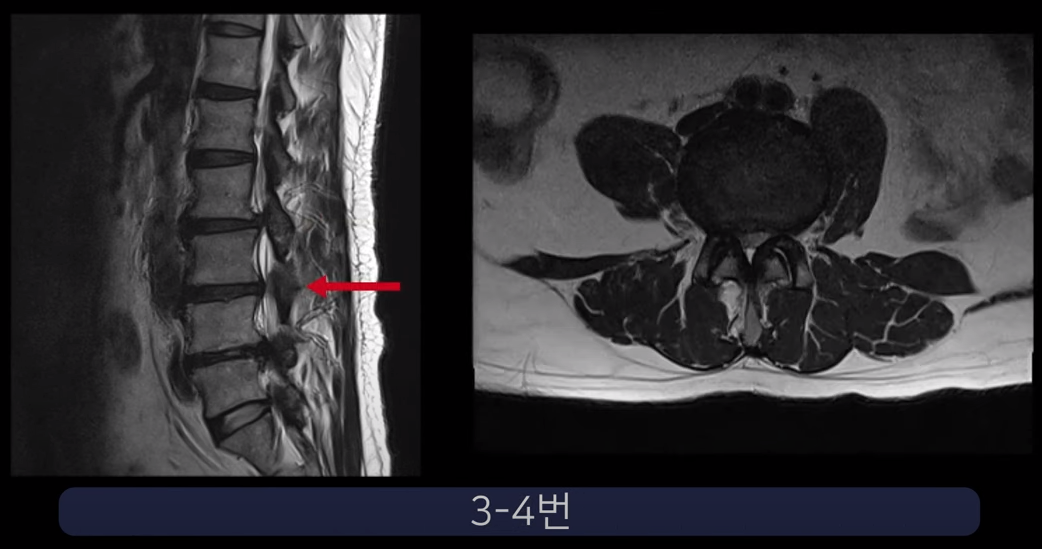

실제 척추관과 추간공이 심하게 막힌 두 환자 케이스를 보여드리겠습니다.

첫 번째 환자분입니다. 이 환자분은 허리 세 마디에 심한 협착이 있습니다. 2-3번, 3-4번, 4-5번 이렇게 척추관이 세 마디가 심하게 막혀있습니다.